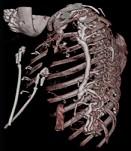

问题 下面一组图像显示的是 ( )

选项 A、奇静脉增粗可见于各种病因引起的上腔静脉梗阻 B、奇静脉增粗可见于各种病因引起的下腔静脉梗阻 C、正常的奇静脉干直径小于1.0cm D、奇静脉弓层面其直径小于1.2cm E、奇静脉扩张

答案 ACDE